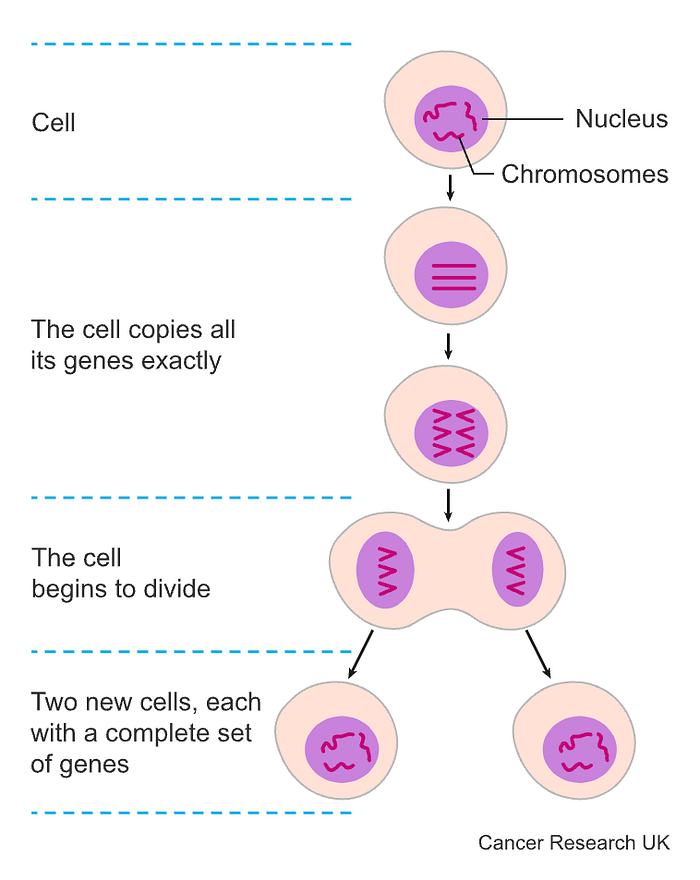

Chemotherapy works by killing any cell that is replicating fast. In cancer, the cells divide super quickly until there is a huge mass of cells, which become a lump, or tumor. Because cancer cells divide much faster than most regular cells, chemotherapy is much more likely to kill them than other cells.

In each living cell is a nucleus, the cell’s control center. The nucleus contains chromosomes, which consist of genes and are the target of chemotherapy drugs. Some drugs may damage the cells at the point of splitting while others damage the cells before they split — while the cells are replicating their genes. You might also have a blend of different chemotherapy drugs which damage cells at different stages of cell division, increasing the chance of killing cancer cells.